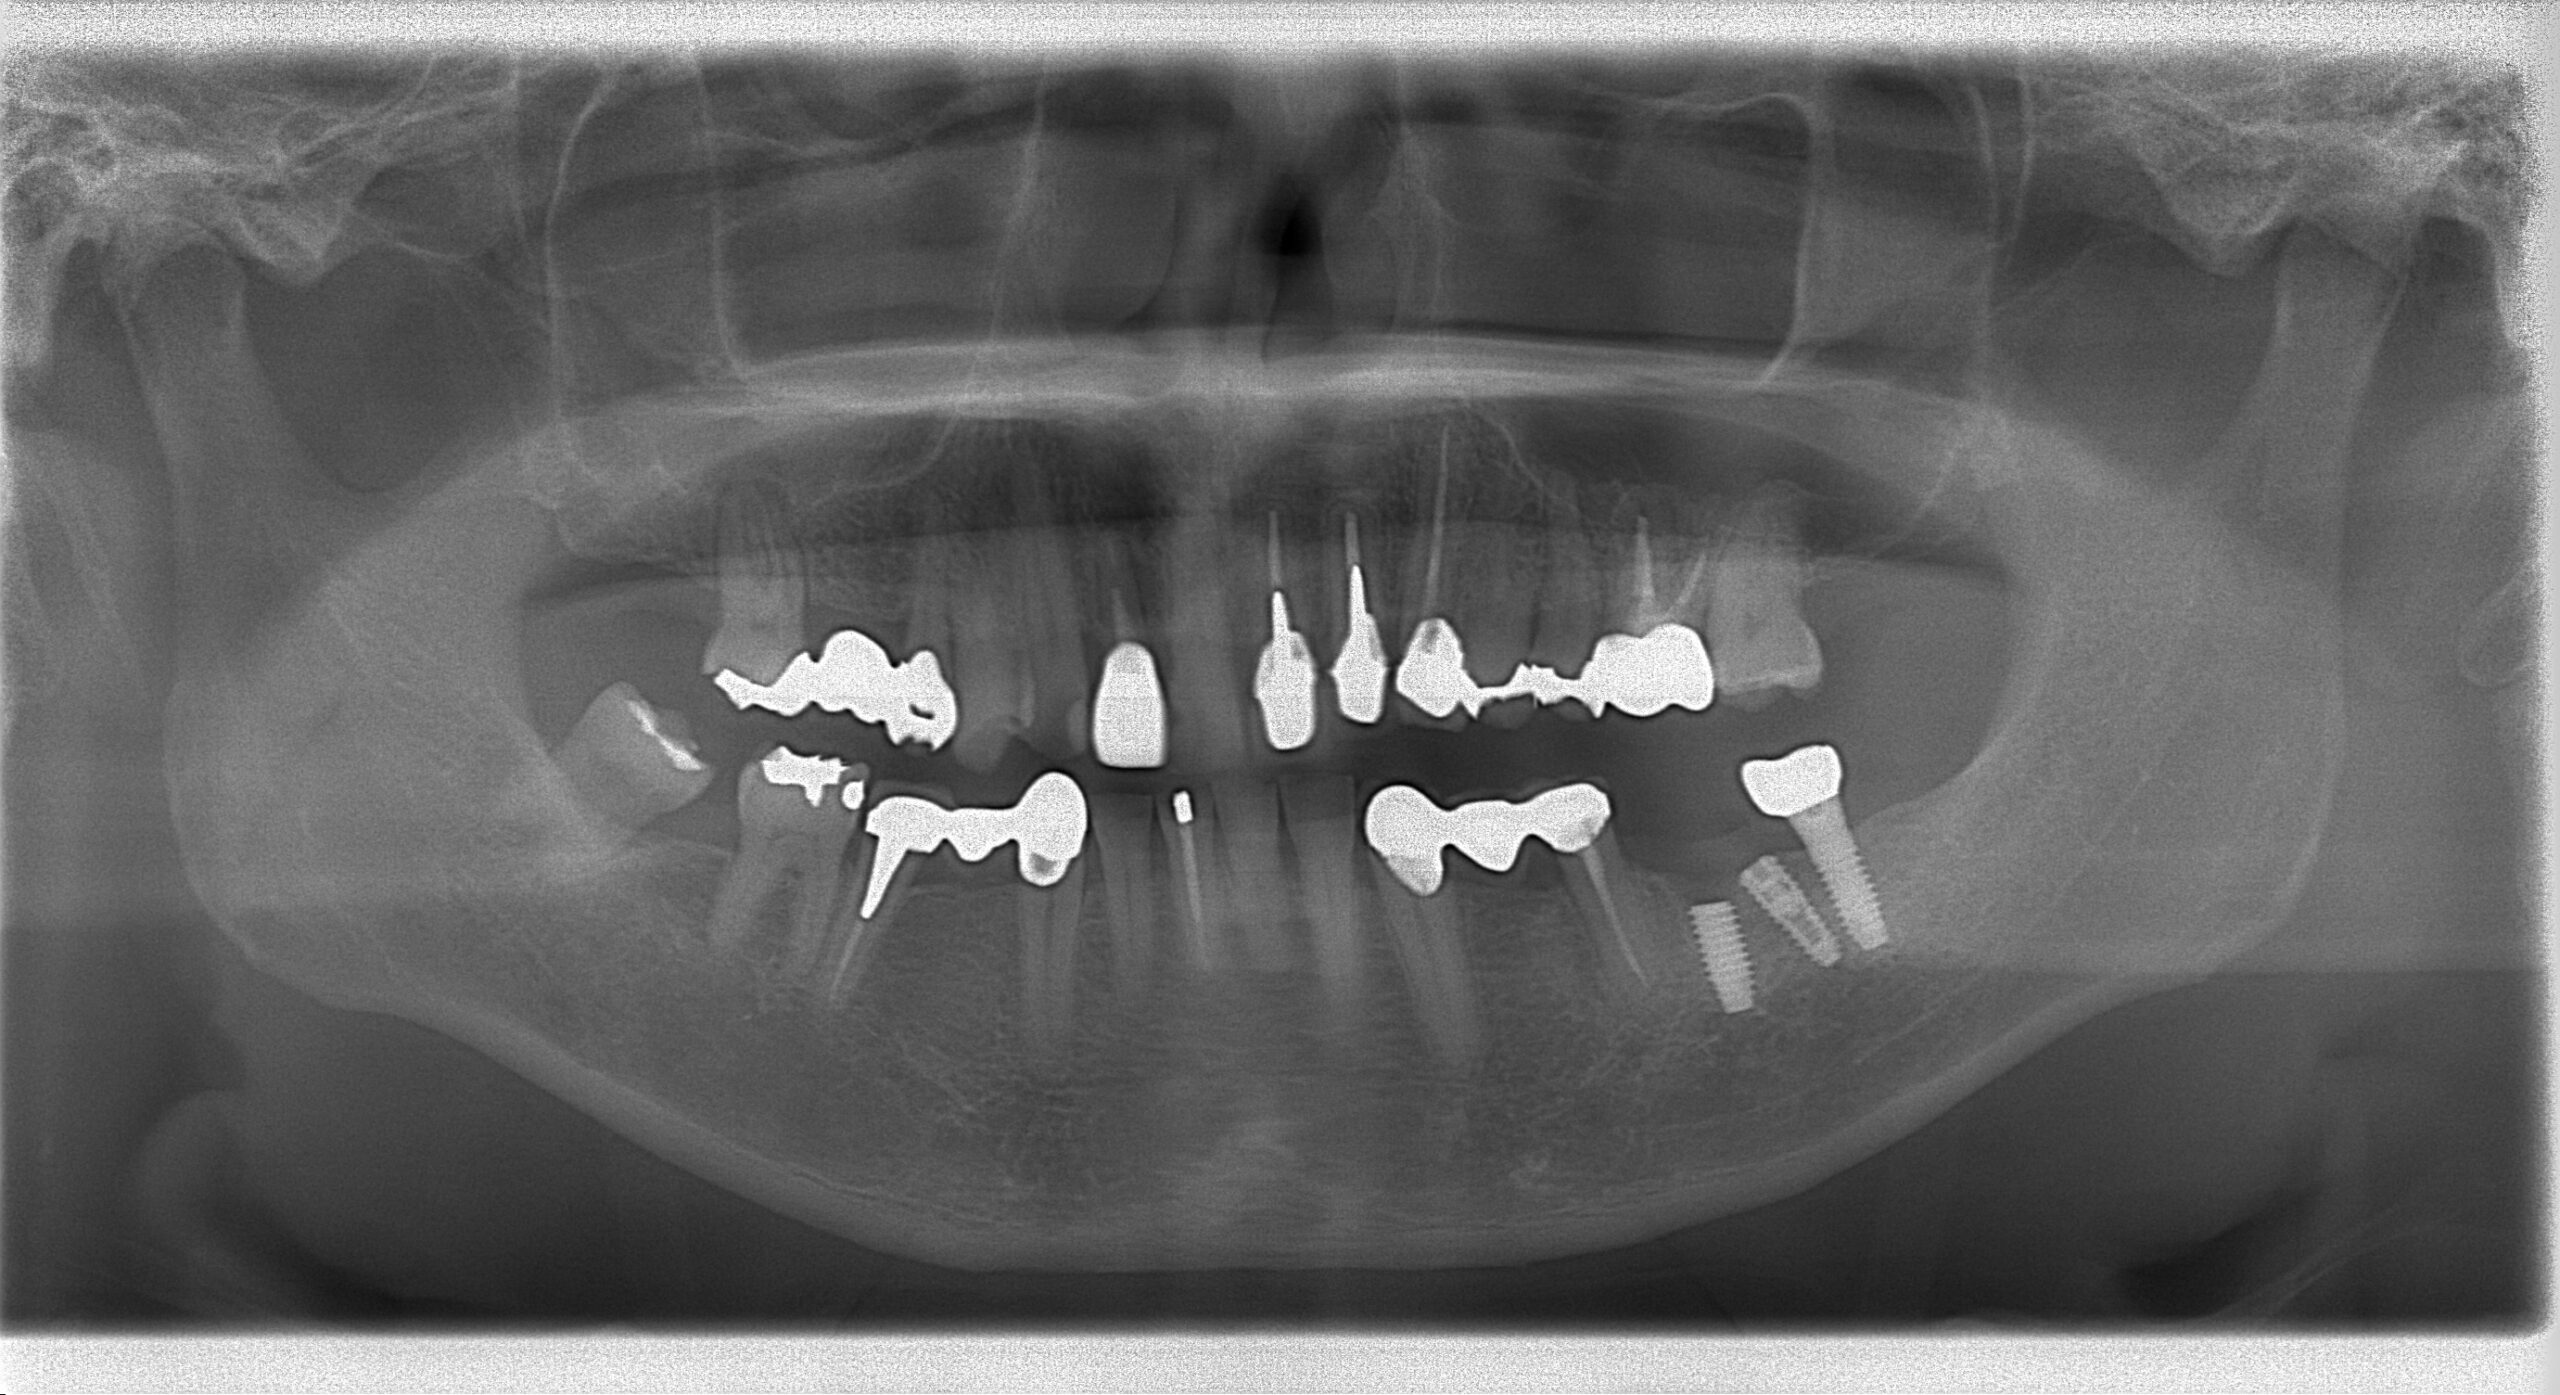

新しいインプラント体埋入後のパノラマX線写真

通常破折したインプラント体を除去して再埋入するかと思いますが、骨結合している

インプラント体を除去するのは既存骨を削除し副作用が大きく、患者様の負担が増すため

今回は間のスペースに埋入しました。

当医院では患者様のベストの治療計画で施術いたします。